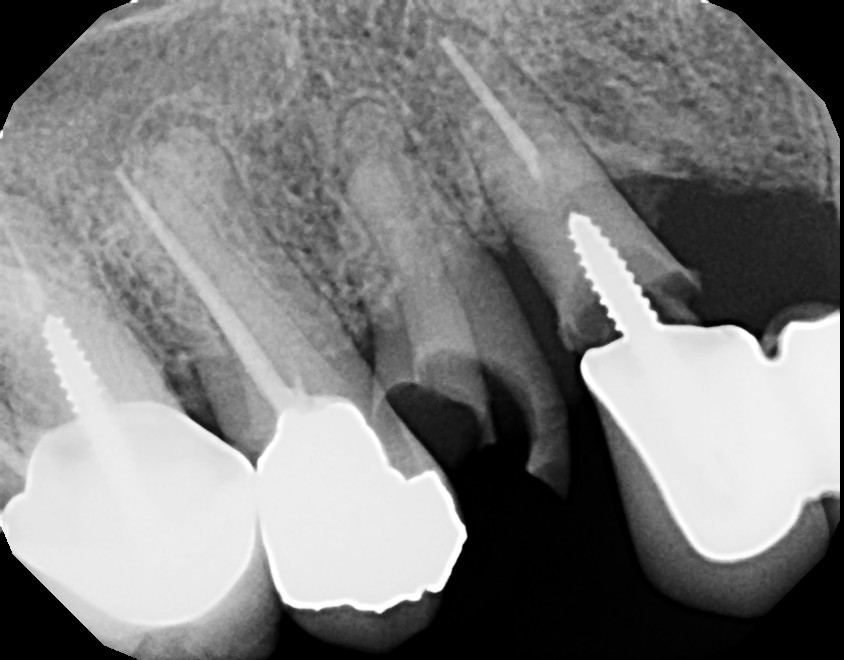

This is a root canal retreatment procedure of 2nd maxillary premolar (tooth #4) due to a missed canal which caused infection. An additional canal was located, both canals were retreated and the tooth will be restored with a crown. The first maxillary molar (tooth #3) needs to be retreated (redone) as well because of infection, due to inadequate root canal therapy. Always ask your general dentist for a referral to an endodontist (root canal specialist) for your root issues.